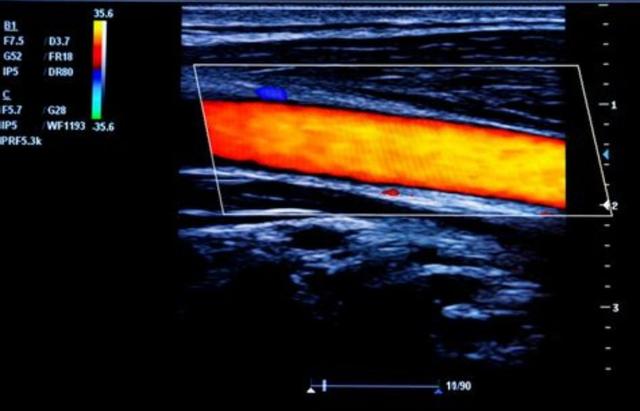

●Problèmes au niveau des vaisseaux sanguins des membres inférieurs. En cas de faiblesse des membres inférieurs, il faut également se demander s'il n'y a pas un problème au niveau des vaisseaux sanguins des membres inférieurs, car les œstrogènes eux-mêmes ont un rôle dans la réduction de la perméabilité des vaisseaux sanguins et dans la diminution du cholestérol sérique, ajouté au facteur de l'âge, on ne peut pas exclure qu'il y ait un problème au niveau de l'irrigation sanguine des membres inférieurs, ce qui conduit à la faiblesse des membres inférieurs des amies, alors il faut faire le point sur cette situation.Echographie vasculaire des membres inférieursEn cas d'affection grave, il peut être nécessaire d'effectuer les examens suivants pour déterminer s'il existe une plaque ou une sténose dans les vaisseaux des membres inférieurs.Angiographie des membres inférieursLa vasculature de l'ensemble des membres inférieurs est ainsi mieux définie.